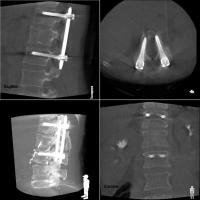

一例として、金属のボルトを骨内に挿入する際に、位置や角度、深さを様々な方向から観察できるほか、装置を回転させて撮影することで、CT画像のような自由な断面像を得ることも可能です。